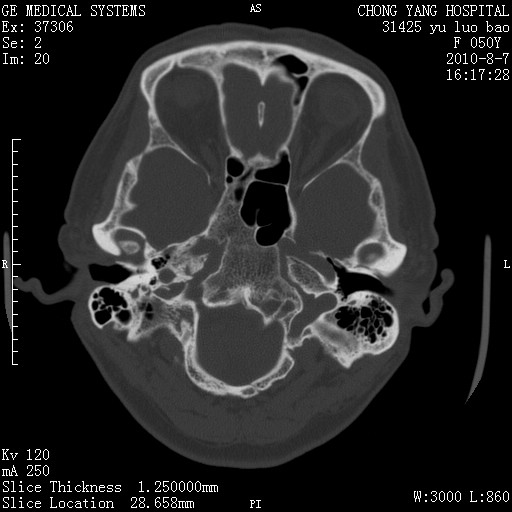

标题: CT28285:听力下降一年,头昏。 [打印本页]

标题: CT28285:听力下降一年,头昏。

右侧桥小脑角去等密度占位,右侧内听道扩大、骨质吸收,考虑:右侧听神经瘤,建议增强检查。

骨窗示右侧内听道扩大,考虑右侧听神经瘤。